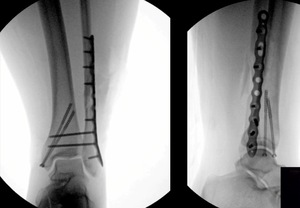

Our Randomized Controlled Trial specifically excluded those, because when I was a resident, syndesmosis injury was kept non-weight-bearing for three months, that was the standard (three months in a cast). Unfortunately, the treatment is sometimes worse than the disease. There is much controversy in terms of weight bearing for syndesmosis injuries, and not as much evidence on this specific injury compared to previously discussed ankle fractures. Figure 7 is a type of fracture we’re referring to: After you fix it, what do you do next?